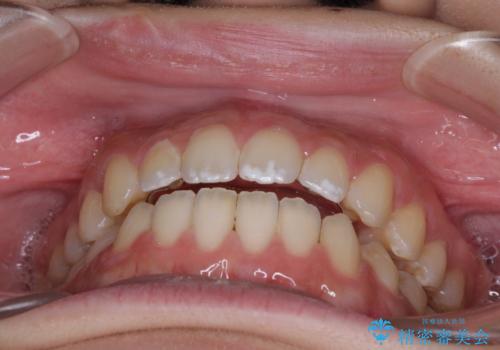

仕上がりとしては、もう少し上下前歯を接触させたかったのですが、ここまで改善されたことで患者様は大変満足され、治療を終えることとなりました。

- 上下前歯の隙間と咬み合わない前歯を気にして来院された患者様です。

開咬の治療は、前歯を閉じるように動かすとともに、上下臼歯を圧下(骨内にめり込ませる)させることで進めて行きます。

開咬とすきっ歯は、舌の突出癖改善が必須となるため、トレーニングを徹底的に行うよう指示しました。